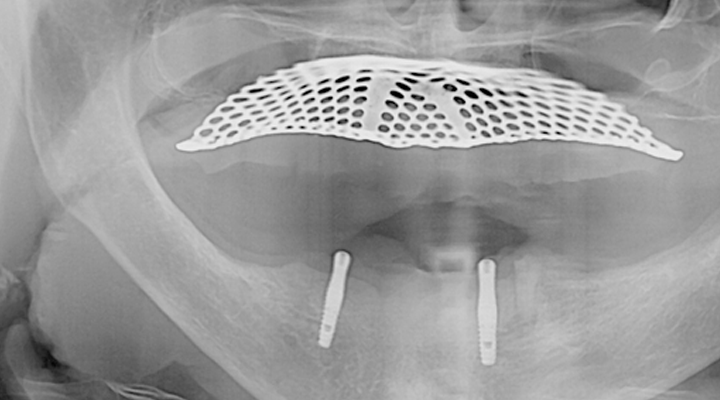

몇 개의 임플란트를 심은 뒤, 완성된 임플란트에 부분 틀니를 연결해 흔들림 없이 안정감 있게 사용할 수 있으며 스스로 탈착은 불가능합니다.

적은 수의 임플란트를 심으면서도 입안의 틀니가 움직이지 않도록 고정해 주어 식사하는 데 부담이 적습니다.